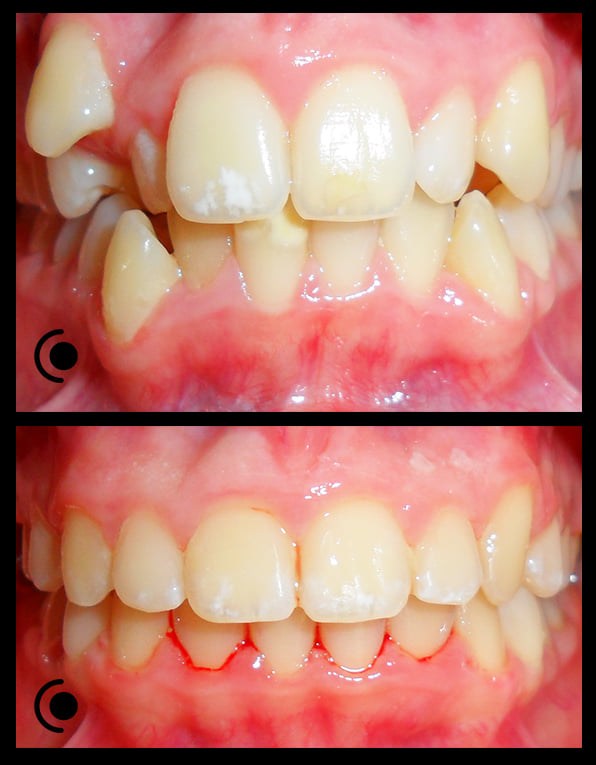

O našoj kvaliteti najbolje govore naši rezultati!

Centar za ortodonciju Petra Džapo